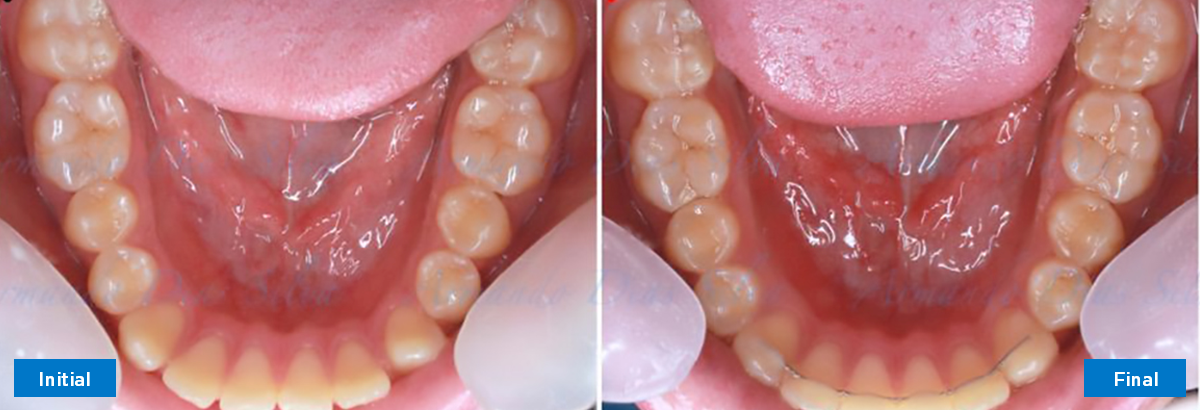

• Molares de clase II

• Diastema

• Espaciamiento leve de las arcadas superior e inferior (deficiencia transversal de 3,45 mm)

• El primer molar superior derecho está en una posición más mesial que el primer molar superior izquierdo

• Deficiencia transversal maxilar leve (3,45 mm)

• Incisivos superiores e inferiores proclinados

• Orientación canina desfavorable

• Desrotar y distalizar los molares superiores

• Retruir los incisivos superiores

• Retroclinar los incisivos inferiores

• Molares de clase I logrados con distalización y sin elásticos

• Sin cambios en la posición del cóndilo

• Sin expansión maxilar, respetando la envoltura periodontal

• Incisivos inferiores retroinclinados, que mejoran la estabilidad a largo plazo